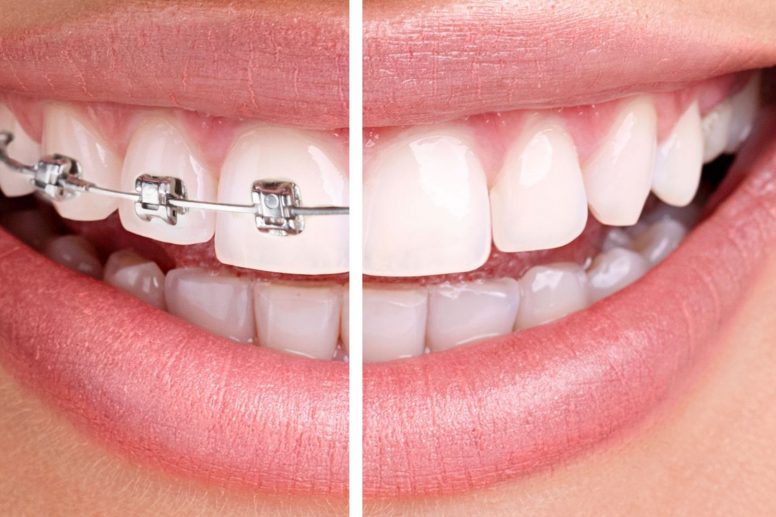

ORTODONŢIE

Ce este ortodonţia? Ortodonţia este specialitatea care se ocupa cu studiul si tratamentul anomaliilor dento-maxilare ce pot fi rezultatul inghesuirilor/spatierilor dentare,discrepantei de marime dintre maxilar …